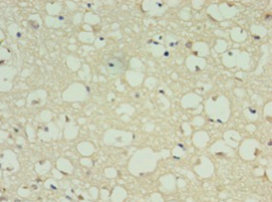

Immunohistochemistry of paraffin-embedded human brain tissue using CSB-PA007182EA01HU at dilution of 1:100